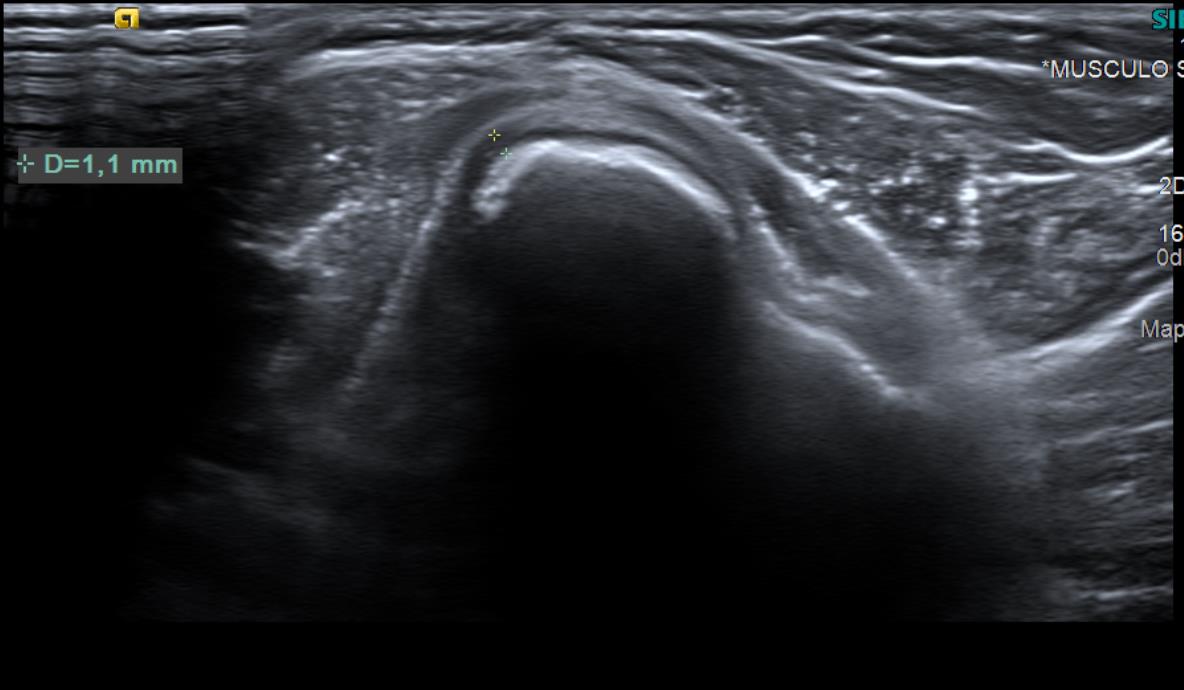

Con el objetivo de no irradiar al escolar, se decide realizar una ecografía desde el centro de salud, para poder obtener una mayor aproximación diagnóstica.

Ecografía: La tumoración referida corresponde a una excrecencia ósea con ribete hipoecoico circunante de 1 mm de espesor, sugestiva de lesión osteocondral.